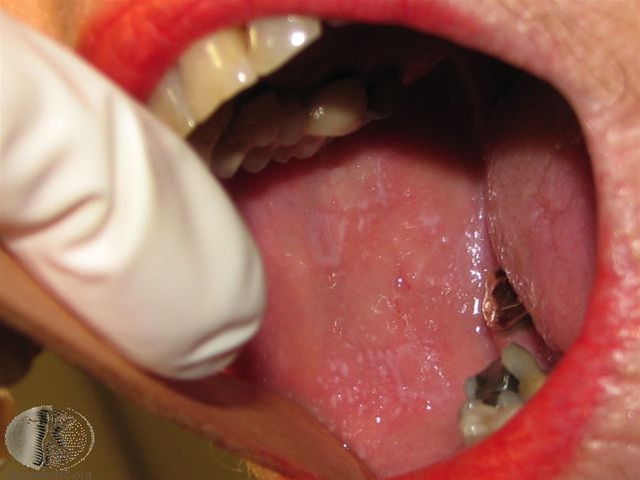

Oral lichen planus, her på tunge.